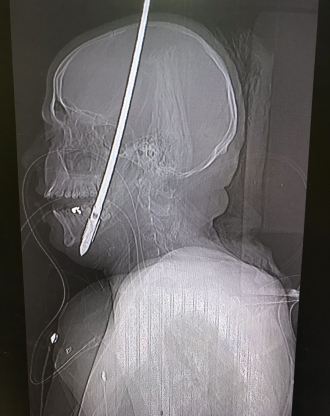

בשבוע שעבר, בעת שנסע ברכבו באזור צומת חורב בכרמל, נורה לעבר נתנאל חץ פלדה המשמש לצייד כרישים ובעלי חיים גדולים. החץ חדר את פניו של נתנאל, אך בנס לא פגע במוחו. באופן מדהים, למרות הפציעה הקשה נתנאל שמר על קור רוח, החזיק את החץ הארוך – שנכנס דרך הלחי ויצא מהלסת התחתונה – ורץ במהירות לחדר המיון של בית החולים כרמל, שם פגש בו האח מלאליק רוחנא. עבור האחרון, המשמש כבר 35 שנים כאח אחראי בחדר המיון, מדובר היה במחזה אותו ראה לראשונה בחייו.

מנהל יחידת פה ולסת בבית החולים כרמל, ד"ר גוסטבו מואיגר, הגיע מיד, ביקש להרדים את נתנאל ושלח אותו לבדיקות סיטי מקיפות בהרדמה. הצילומים התלת מימדיים הדהימו את ד"ר מואיגר וגם את יתר חברי הצוות. "ראינו את חץ הפלדה הענק, בגודל 60 סנטימטרים ובעובי של 70 מילימטרים חודר מלחי ימין, עובר את הפה והלסת התחתונה, ויוצא החוצה. זה היה פשוט נס איך החץ לא פגע במוח, בעיניים או באיברים קריטיים הנמצאים בראש", ציין ד"ר מויאגר.

אלא שכאן לא נגמרה הדרמה. בתחקיר שעשה ד"ר מויגר כדי להוציא את החץ, התברר לו כי הוא מורכב משני חלקים המחוברים בהברגה צמודה. אחד החלקים משמש לחדירת החץ לגוף, והחלק השני, הקדמי, אמור להיפתח בתוך גוף החיה אותה צדים, בצורת פטרייה וחצים קטנים וחדים הננעצים ותופסים את הקורבן באופן בלתי ניתן לשחרור. "אם פטריית החיצים היתה נפתחת חלילה, היא היתה קורעת לנתנאל את כל אברי הפנים וכלי הדם הגדולים של הצוואר", הסביר ד"ר מויגר, "במקרה כזה זה עניין של דקות ספורות עד שהוא היה מדמם למוות".

בניתוח חירום תפס ד"ר מויגר את פטריית החצים כדי שלא תיפתח, ובאמצעות ציוד כירורגי עדין ומדויק שלף את חץ הפלדה החוצה. "בניתוח ביצענו שחזור מדויק של כל רצפת הלסת התחתונה, תוך שאנו מקפידים לשמור לנתנאל על יכולות האכילה, השתייה והדיבור", הסביר ד"ר מויגר.